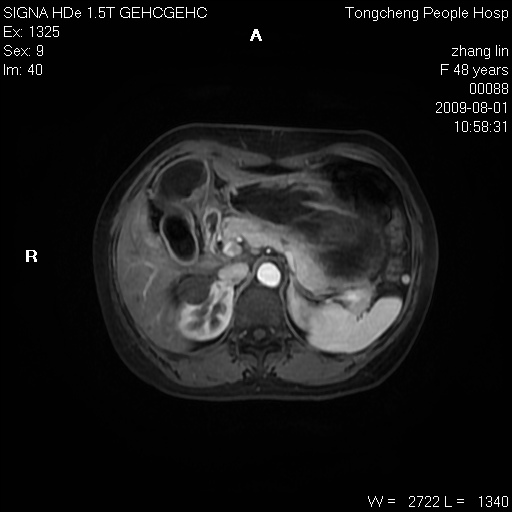

女,48岁。健康体检,彩超发现右肾占位性病变。平素健康。

临床诊断:右肾占位性病变,性质待定(囊肿?肿瘤?)。

上中腹部mr平扫+增强扫描,图像如下:

右肾上极见一类圆形病灶,t1wi呈等信号t2wi呈等高混杂信号,三期增强无强化,边界清---考虑囊肿出血。

同反相位均表现为等信号,病变无强化,考虑含蛋白的囊肿可能,弥散加权相或许有些帮助,